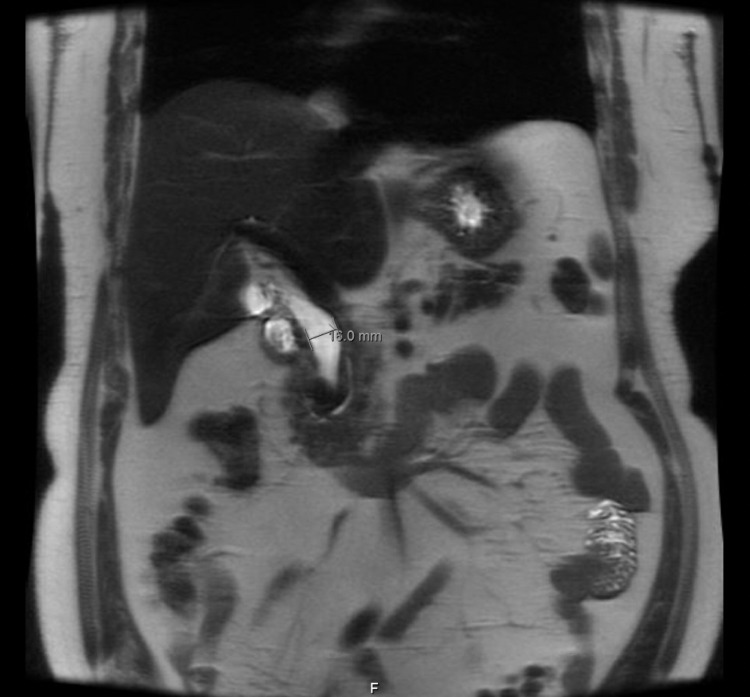

MRCP was done, which showed a dilated CBD measuring up to 16 mm due to the effect of PAD strictly adjacent to its distal portion that is associated with moderate hepatic steatosis and presence of gallstones without evidence of cholecystitis (Figure 3).